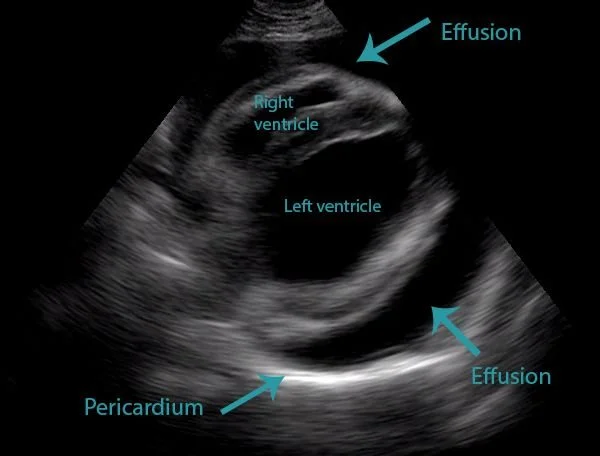

Pericardial effusion in a dog.

TFAST

Thoracic focused assessment: Primary aim is rapid identification of pleural or pericardial effusion and pneumothorax. It supports decisions on thoracocentesis, pericardiocentesis, oxygen therapy, and monitoring. Core windows include pericardial site (PS), pleural sites (PL), and diaphragmatico‑hepatic interface. Reporting involves binary calls (positive/negative effusion or pneumothorax by site and overall TFAST), artefact documentation (sliding, B‑lines, lung point, curtain sign), and escalation to the vet with clips for drainage or monitoring.